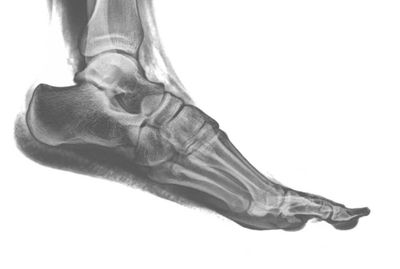

A chiropodist is a regulated foot care specialist in Ontario. They are licensed by the Ontario College of Chiropodists.